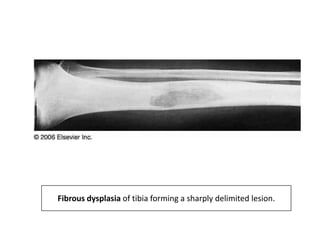

Fibrous dysplasia and related lesions

• First described by Albright in 1937.

• Most common of the fibro-osseous tumours.

• It is a benign medullary fibro-osseous lesion which may

involve one or more bones.

• It has been likened to a localized developmental arrest-

• X ray-

• Classic groundglass appearance.

• Can be radiolucent or radiodense depending on

amount of bone present and degree of

mineralization.

• In appendicular skeleton- Well defined margins of

the lesion and surrounded by rim of sclerotic bone.

• Craniofacial skeleton- less well defined and blends

with surrounding bone.

Fibrous dysplasia of tibia forming a sharply delimited lesion.